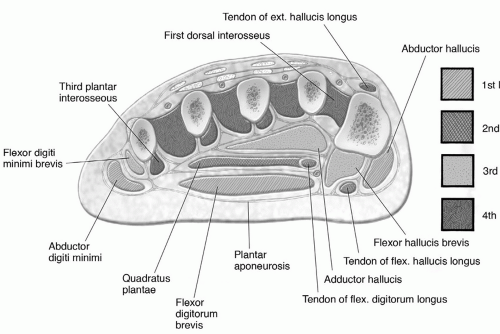

Forefoot Mri Anatomy

mavink.com

mavink.com

Ankle And Foot | Radiology Key

radiologykey.com

radiologykey.com

foot ankle radiology fig radiologykey